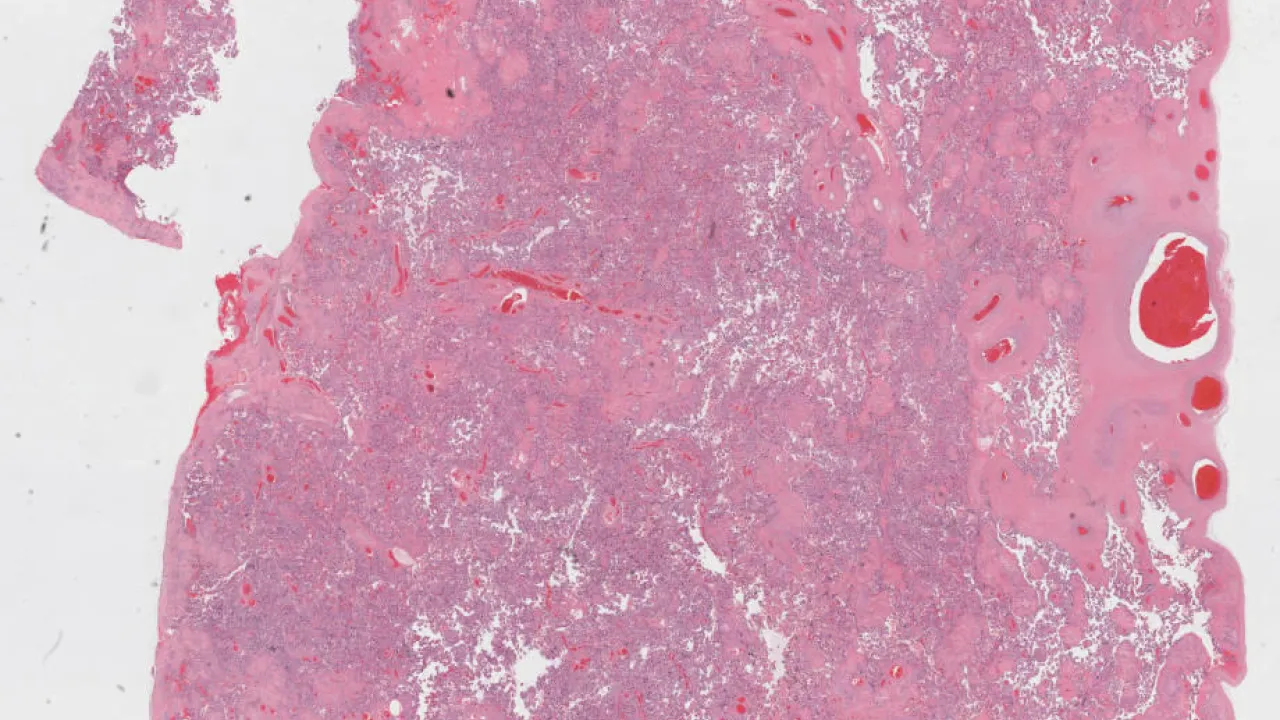

Pulmonary artery, Pulmonary arterial thromboembolism